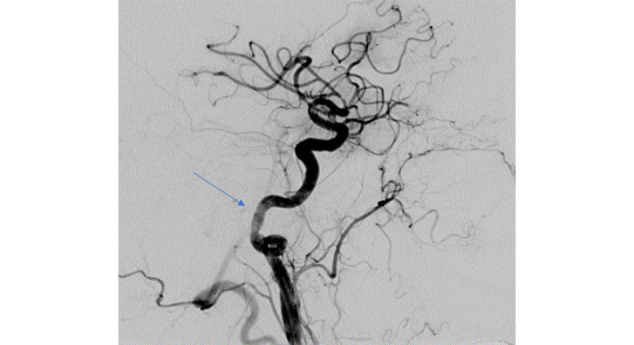

It is not uncommon for patients to suffer from both acute myocardial infarction and acute stroke during the hospitalization. According to some studies, about 12% of the elderly population initially hospitalized for acute ischemic stroke also develop type-1 acute myocardial infarction during the same hospitalization. On the other hand, about 0.9% of patients hospitalized for acute coronary syndrome develop acute stroke during the same hospitalization1. The therapeutic approach to such "overlapping" patients is challenging, especially if we also take into account a high risk of bleeding and/or active bleeding. Therefore, interdisciplinary collaboration between cardiology, neurology and interventional neuroradiology is of key importance. Timely intervention and adequate concomitant drug therapy (primarily antiplatelet and anticoagulant therapy) determine treatment outcomes and long-term results. In our recent clinical work, we treated a patient with a series of acute cardiac and cerebral incidents presenting multiple therapeutic dilemmas, who ultimately had an unfavourable neurological outcome.